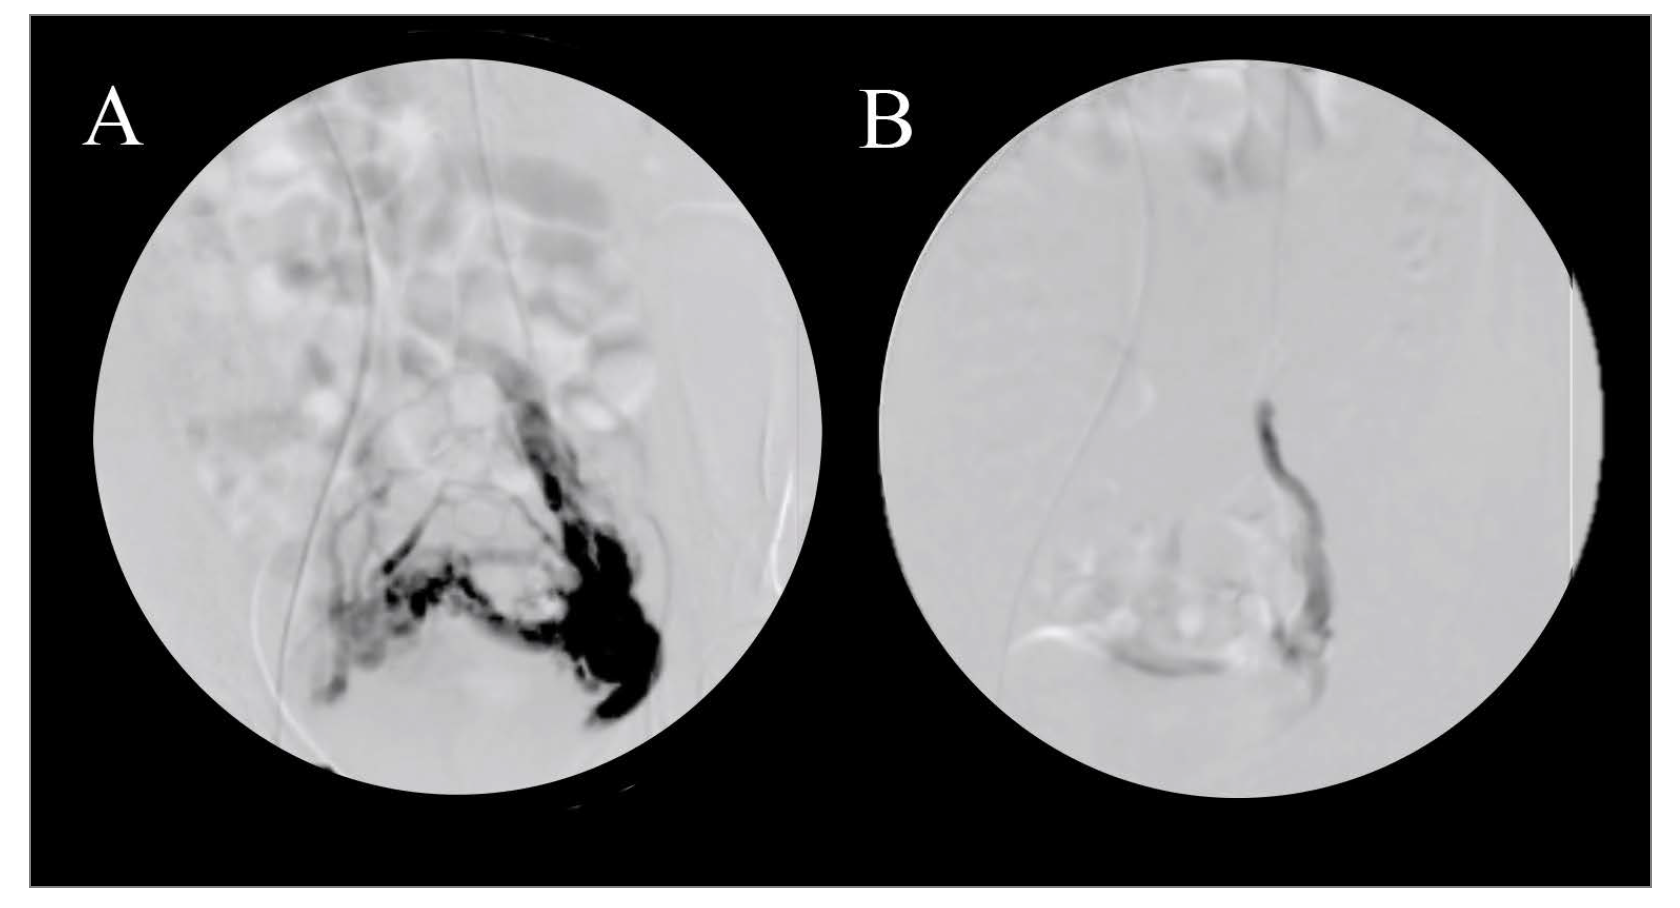

There are several traditional and laparoscopic surgical options with reported success in management of PCS symptoms, but these surgeries often involve the removal of uninvolved bystander structures and the risk of surgical complications and possible fertility issues, which is why endovascular treatment has been the most agreed-upon treatment for PCS.12,21,22 Transcatheter embolization is a safe and reliable treatment modality for PCS that may conveniently be performed at the same time as diagnostic venography. During transcatheter embolization, a catheter is advanced to the ovarian and/or hypogastric vein, and the symptomatic vessel is embolized using Gelfoam (Pfizer) (Figure 2), sclerotherapy, coil, or a combination of materials.